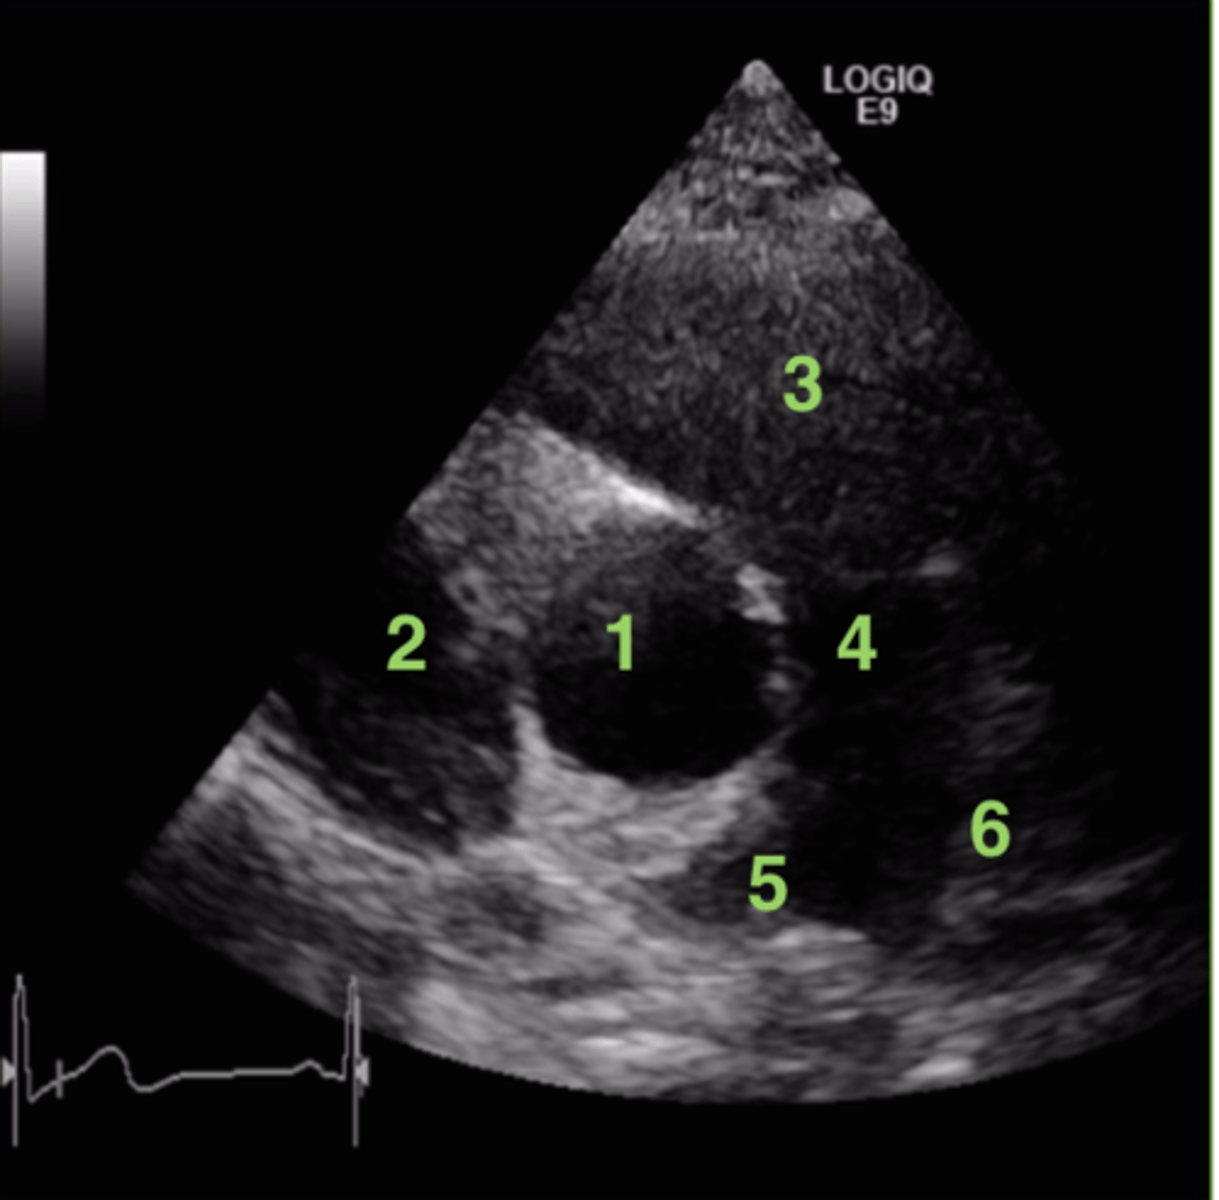

MV 3CA (left leaflet)

posterior mitral valve leaflet

MV 3CA (right leaflet)

anterior mitral valve leaflet

AoV 3CA (left cusp)

non-coronary cusp

AoV 3CA (right cusp)

right coronary cusp

anterior tricuspid valve leaflet

top leaflet

septal/medial tricuspid valve leaflet

bottom leaflet

anterior mitral valve leaflet

top leaflet

posterior mitral valve leaflet

bottom leaflet